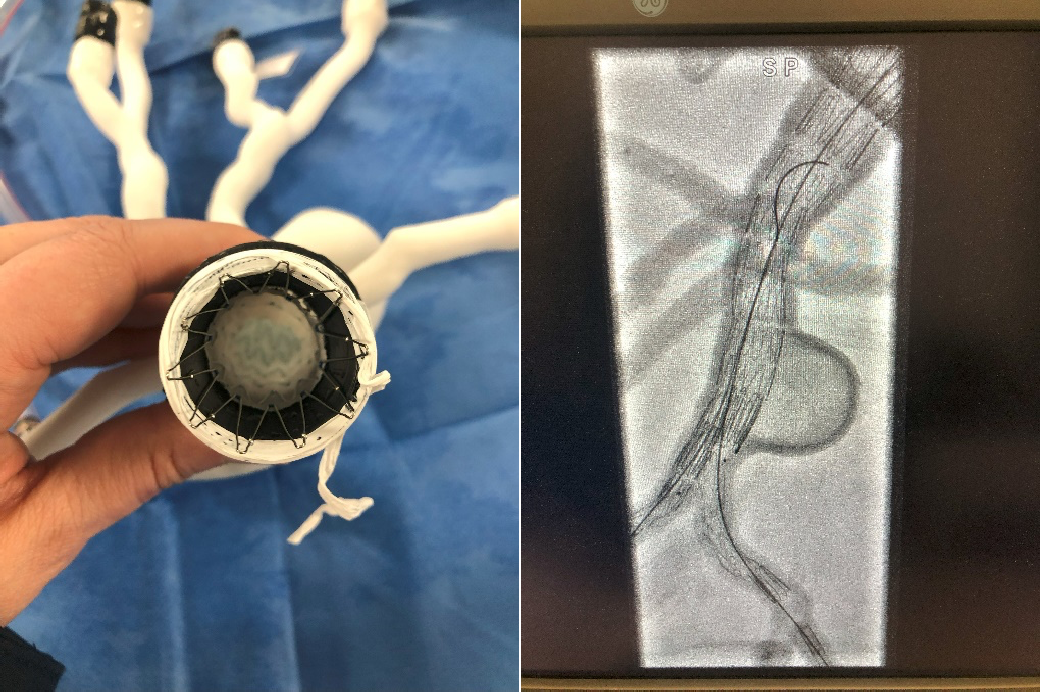

Depuis janvier 2025, les modèles 3Deus intégrés au simulateur sont testés en conditions réelles au sein du MALIC à l’Hôpital Marie Lannelongue, un centre pionnier en simulation chirurgicale qui reproduit fidèlement les conditions d’une intervention assistée par imagerie. Cet environnement a offert un cadre idéal pour évaluer la fidélité biomécanique et sensorielle des modèles.

Ils offrent des performances améliorées par rapport aux modèles précédents, notamment en termes de déformabilité, d’étanchéité et de radio transparence et ce même après plusieurs pose d’endoprothèse. Ces avancées ont permis notamment la pose successive de différentes endoprothèses en salle hybride conforme aux exigences techniques, tout en garantissant un réalisme haptique. Si certains critères restent encore à optimiser, les premiers résultats prometteurs ont permis de collaborer à la rédaction d’un cahier des charges fonctionnel et technique rigoureux dont la qualification et la caractérisation seront mis en œuvre au cours de cette collaboration.